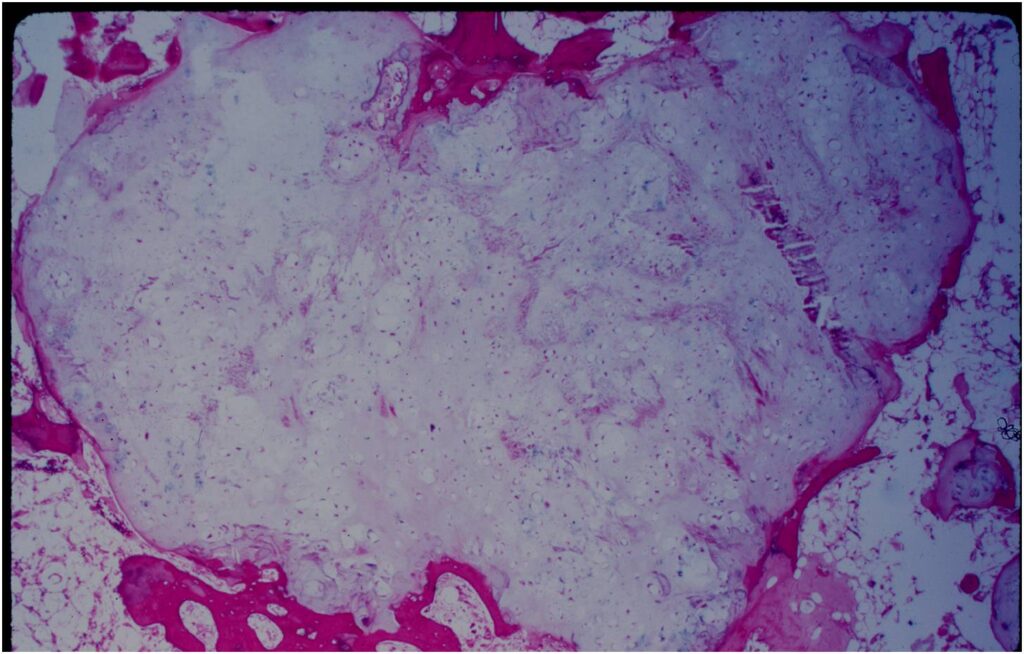

Gross Pathology

- Fragments of enchondroma after curettage are bluish white and glistening hyaline cartilage

- There may be yellow calcified foci

- Cartilage grows in a lobular manner and hence in a completely resected specimen there will be local lobules of mature cartilage

Microscopic Pathology

- Enchondromas are well defined lesions with cartilage arranged in lobules that are separated by fibrovascular septa

- Enchondral ossification may occur around periphery of lobules and when calcified appear as “Rings and Arcs” on X-rays